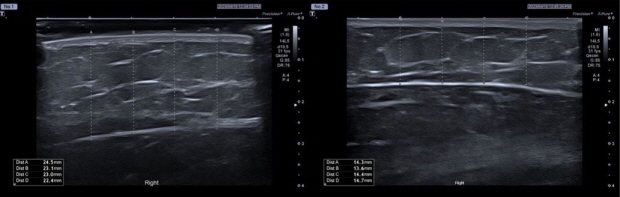

연구에 따르면 브이올렛 5mg/mL, 2.5mg/mL를 팔뚝 부위에 8주에 걸쳐 3차례 시술한 뒤 20주간 관찰한 결과 피하지방의 두께가 각각 평균 7.49mm, 4.68mm 감소한 것으로 나타났다. 상완 팔둘레 길이 역시 투여 후 20주 시점에 평균 1.55mm, 1.1mm 감소한 것으로 확인됐다.